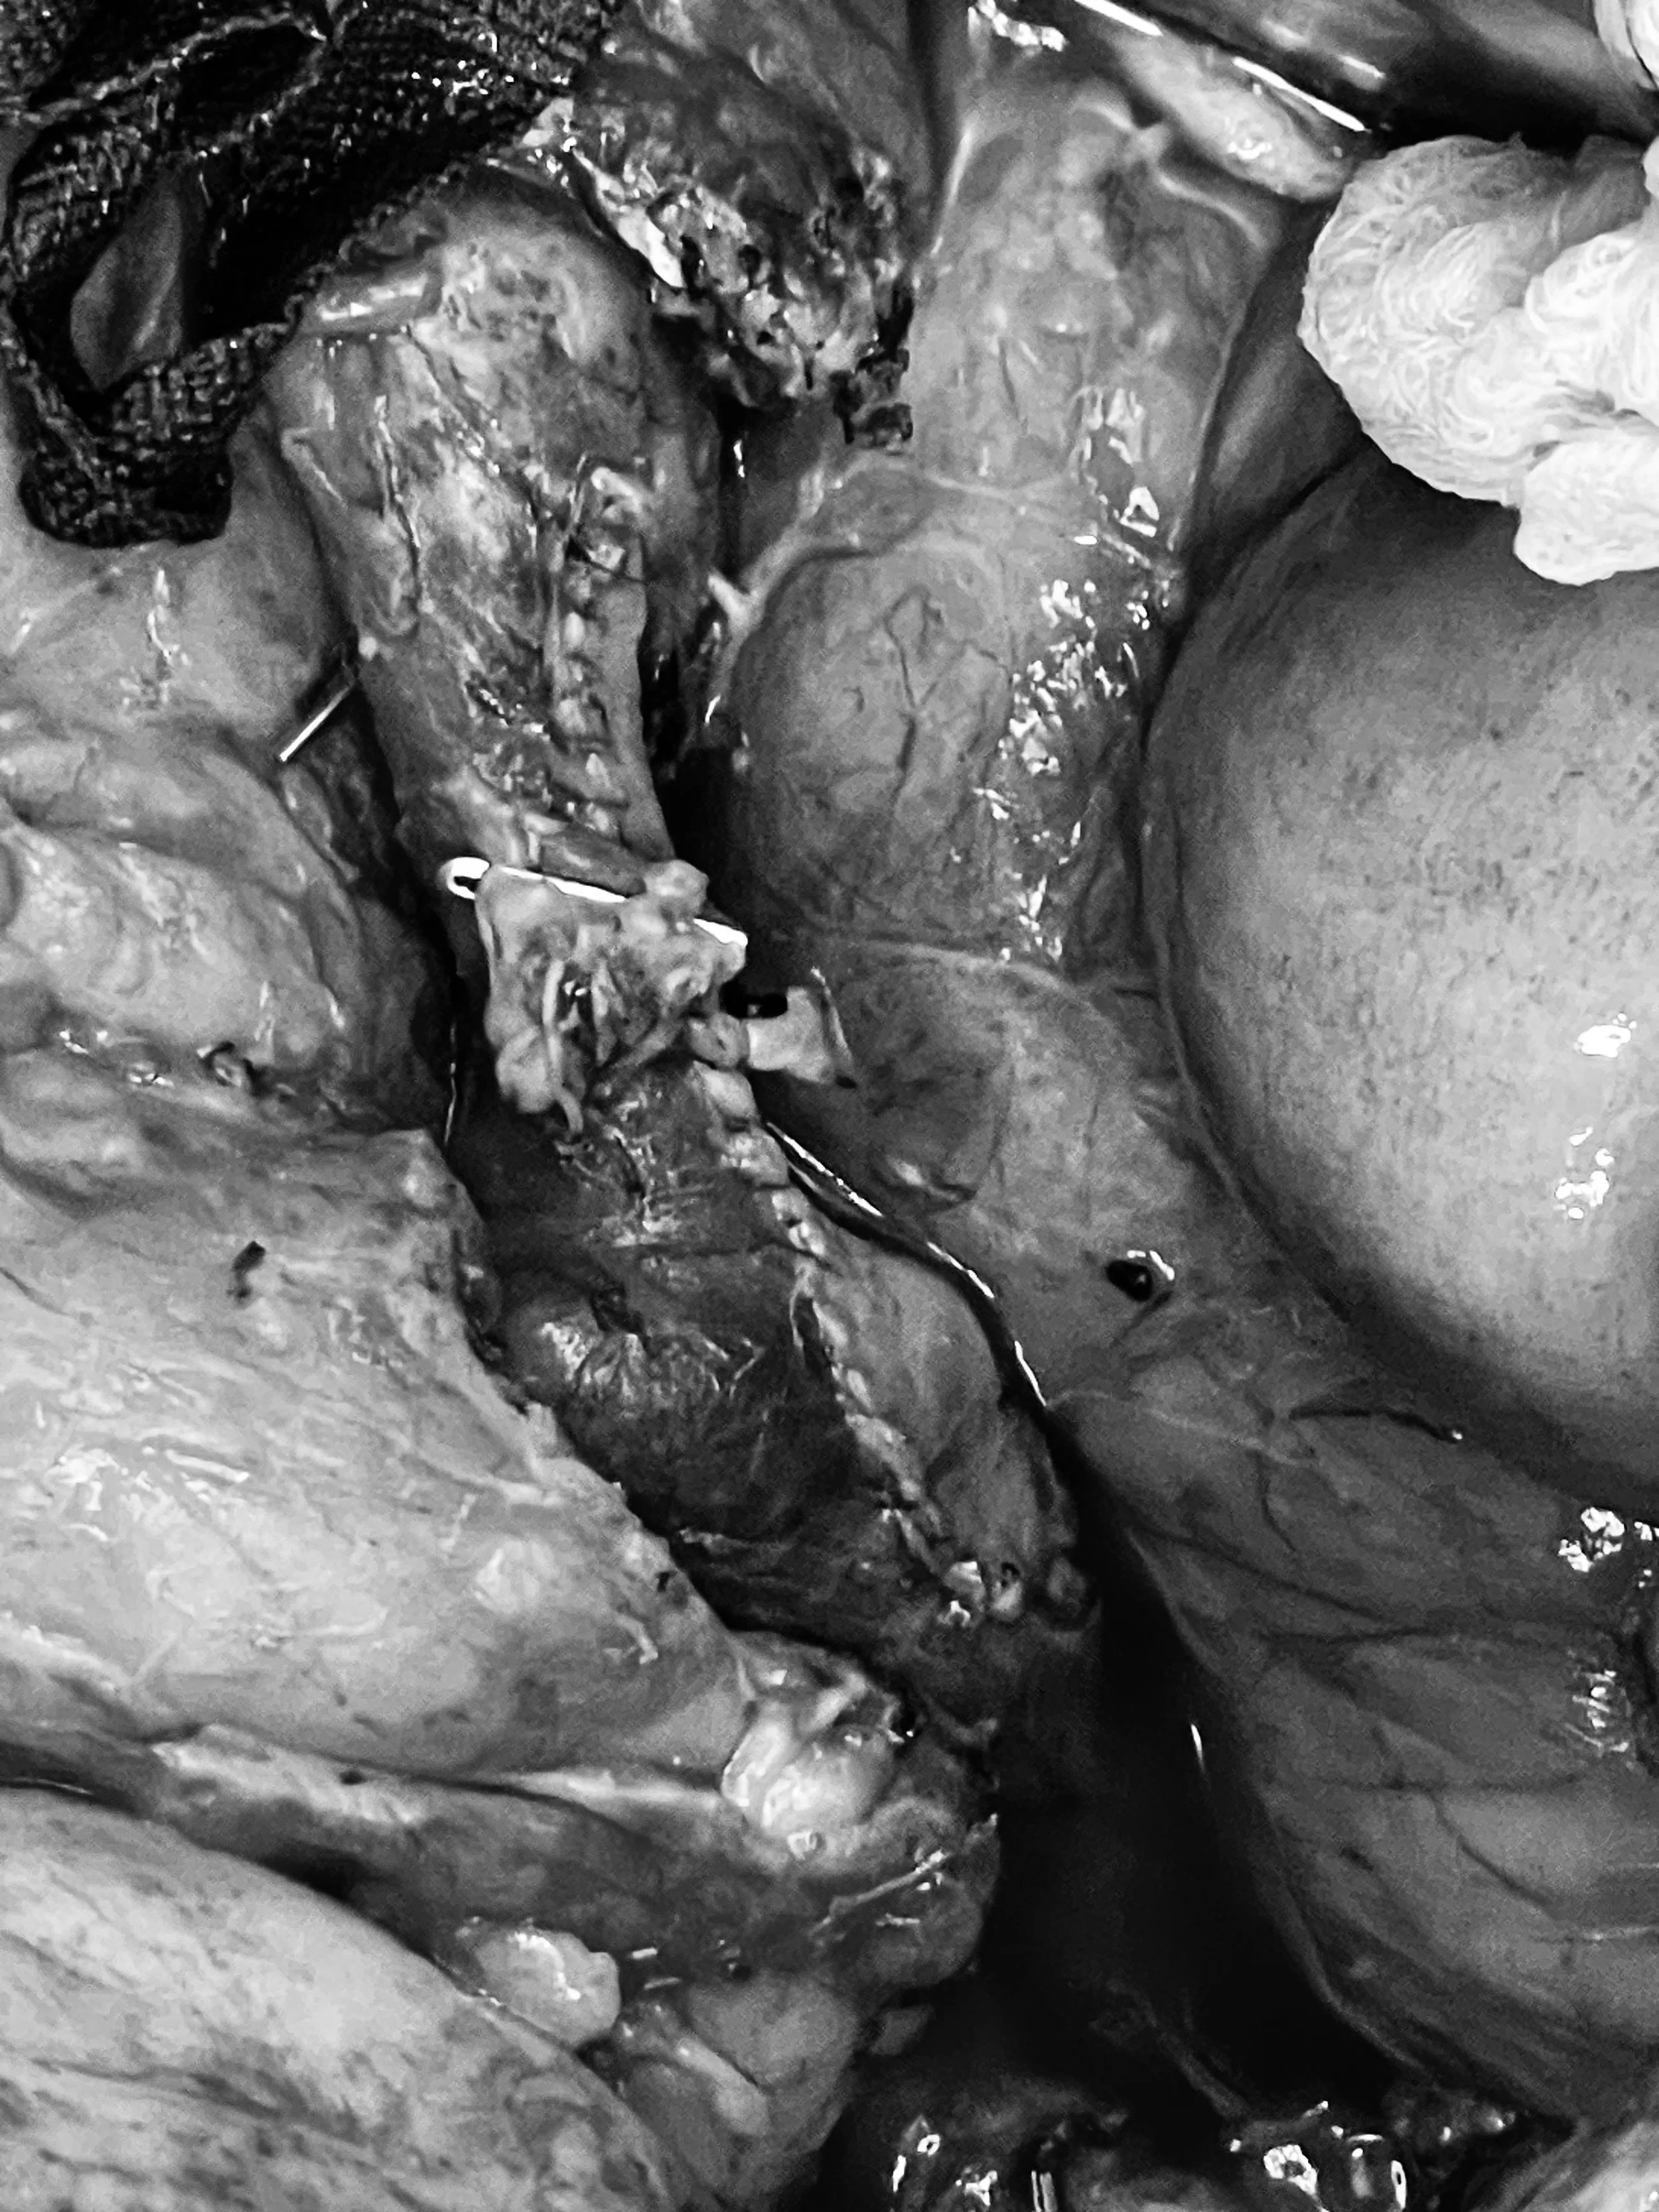

Aortic reconstruction is a major vascular surgery used to repair the aorta, the body’s largest artery, when it becomes damaged by an aneurysm (bulging) or occlusive disease (blockage). This procedure is performed through an open surgical approach to allow for a direct reconstruction of the affected aortic segment.